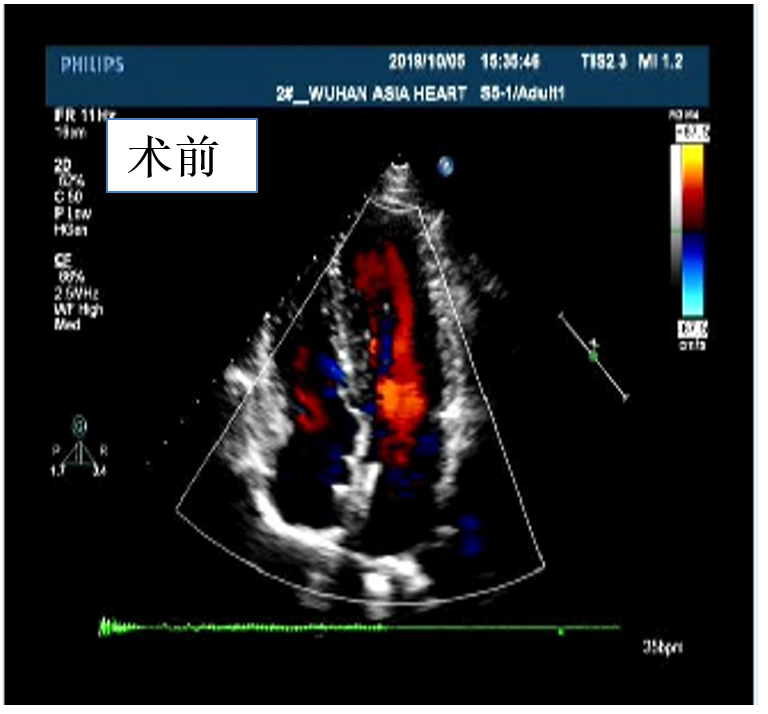

行心脏彩超:显示房水平中量右向左分流,门诊遂以“中央型房间隔缺损”收入院

图片

随访结果

2020年08年04日来我院进行手术后复诊,行心脏彩超